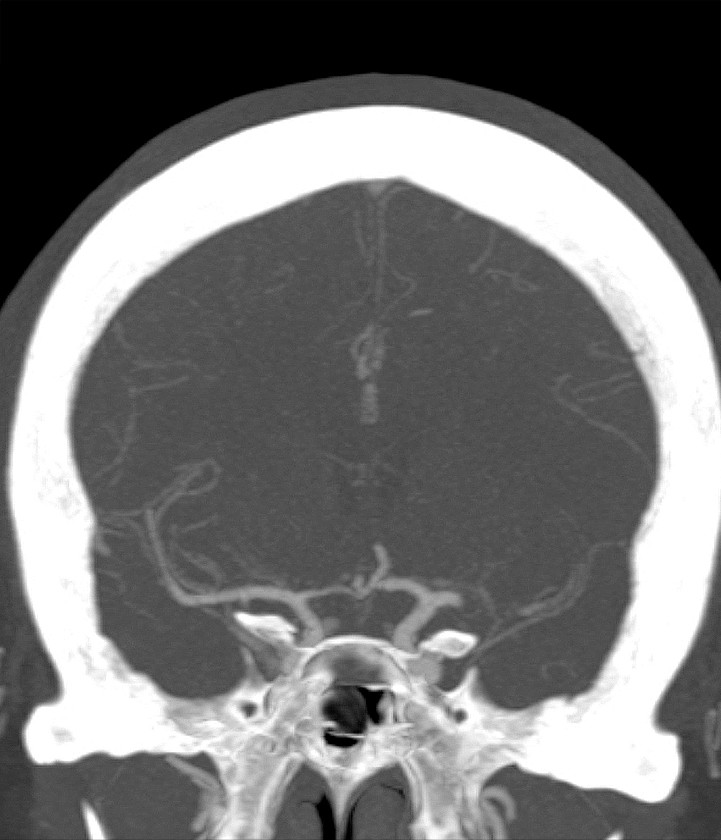

Myren-Svelstad S, Hammer TA, Idicula TT. Early thrombectomy of a proximal middle cerebral artery occlusion leading to complete recovery with no infarct. Case Rep Neurol 2017; 9: 76 - 80. [PubMed][CrossRef]

Vi vil takke for en fin kasuistikk som til fulle viser hvilket potensiale mekanisk rekanalisering (trombektomi) har ved cerebral storarterieokklusjon. Antall som må behandles for én pasient skal komme gjennom et hjerneinfarkt med mindre grad av funksjonshemming (Number Needed to Treat, NNT), er 2,6. I Norge gjennomføres trombektomi per dags dato ved fem sykehus, og to nye sykehus skal starte med trombektomi fra neste år.

Ved St. Olavs Hospital synes man å ha en meget konservativ utvelgelse av pasienter for trombektomi. Forfatterne skriver at behandlingen vanligvis ikke gjøres ved NIHSS-skår < 10. Vi mener i overenstemmelse med publiserte metaanalyser at en slik høy grense for intervensjon gjør at endel pasienter går glipp av svært viktig akuttbehandling. Målet med trombektomi er å begrense skadevolumet i hjernen, ikke å reperfundere et hjernevolum som allerede er nekrotisk. Ved de andre trombektomi-sentrene i Norge vektlegges derfor CT/MR penumbra-vurdering, kollateralsirkulasjon og eventuelt diffusjonsfunn på MR sterkere enn selve NIHSS-skåren når indikasjonen for trombektomi stilles. I OUS-materialet fra 2017 hadde 39 av totalt 120 pasienter (32,5 %) NIHSS-skår < 10 på indikasjonstidspunktet (abstrakt presentert på Nevrodagene 2018 ved B. Enriques og medforfattere). Disse hadde klinisk og radiologisk et stort truet penumbravolum. Ved å bruke høy NIHSS-skår som indikasjon og ikke en individuell fysiologisk tilnærming vil trolig for få pasienter bli behandlet og det samlete resultatet etter trombektomi bli vesentlig dårligere enn det kunne ha vært.

Vi takker Anne Hege Aamodt og medarbeidere for en hyggelig og viktig kommentar. Beklageligvis ligger pasientkasuistikken noe tilbake i tid, utarbeidelse av manuskript likeså. I Trondheim benyttes CT/MR for vurdering av penumbra og kollateralsirkulasjonen vektlegges. At NIHSS-skår ikke kan benyttes som indikasjon alene er selvsagt, og denne misforståelsen beklager vi. Samtidig bør det være et visst nevrologisk utfall før en invasiv prosedyre utføres. Ved St. Olavs hospital gjøres i dag normalt ikke trombektomi ved NIHSS-skår ≤ 5, men alle pasienter som kan være kandidat til trombektomi, får en individuell vurdering, også de med lavere NIHSS-skår.